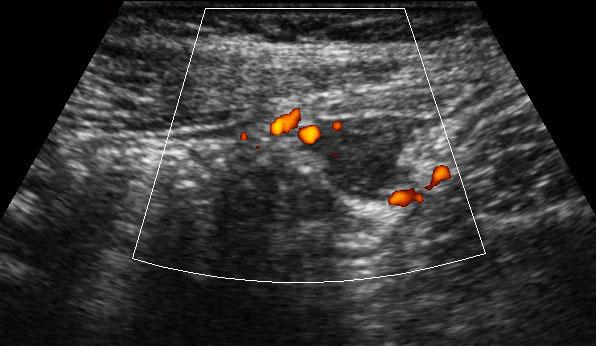

Polyp tuyến

Một polyp đại tràng (mũi tên) được phát hiện trên cả CT và nội soi đại tràng, tuy nhiên do tình trạng gập góc liên quan đến dính ruột, polyp nằm ngoài tầm với của dụng cụ sinh thiết.

Các bác sĩ phẫu thuật cần thêm bằng chứng trước khi tiến hành cắt đoạn ruột qua nội soi ổ bụng.

TVUS cho thấy một khối trong lòng ruột, hình bầu dục, đặc, bờ rõ, không đồng nhất, tăng sinh mạch máu (mũi tên) với đường kính 1,5 cm.

Bệnh nhân được phẫu thuật cắt đoạn ruột, kết quả giải phẫu bệnh cho thấy polyp tuyến ác tính.